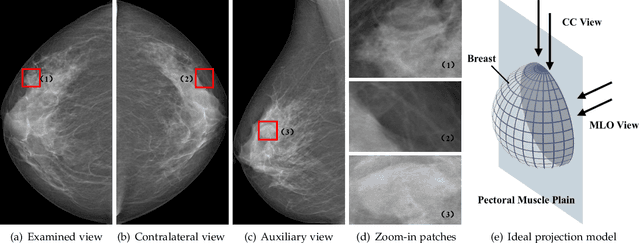

Abstract:Mammogram mass detection is crucial for diagnosing and preventing the breast cancers in clinical practice. The complementary effect of multi-view mammogram images provides valuable information about the breast anatomical prior structure and is of great significance in digital mammography interpretation. However, unlike radiologists who can utilize the natural reasoning ability to identify masses based on multiple mammographic views, how to endow the existing object detection models with the capability of multi-view reasoning is vital for decision-making in clinical diagnosis but remains the boundary to explore. In this paper, we propose an Anatomy-aware Graph convolutional Network (AGN), which is tailored for mammogram mass detection and endows existing detection methods with multi-view reasoning ability. The proposed AGN consists of three steps. Firstly, we introduce a Bipartite Graph convolutional Network (BGN) to model the intrinsic geometric and semantic relations of ipsilateral views. Secondly, considering that the visual asymmetry of bilateral views is widely adopted in clinical practice to assist the diagnosis of breast lesions, we propose an Inception Graph convolutional Network (IGN) to model the structural similarities of bilateral views. Finally, based on the constructed graphs, the multi-view information is propagated through nodes methodically, which equips the features learned from the examined view with multi-view reasoning ability. Experiments on two standard benchmarks reveal that AGN significantly exceeds the state-of-the-art performance. Visualization results show that AGN provides interpretable visual cues for clinical diagnosis.